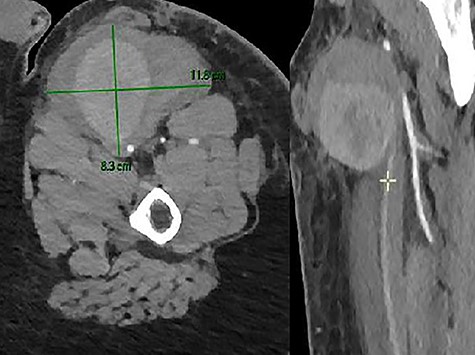

Unfortunately, in the meantime, he presented to the emergency room for a swelling of his left thigh since the morning. He had no pain. He was hemodynamically stable. His hemoglobin was 13 g/dl. We examined a large pulsatile mass of the left upper leg. The CTA showed a PSA (8.3 × 10.7 × 9 cm) of his left SFA and a hematoma with active bleeding on the anterior aspect of the left thigh, in close contact with the left SFA (Fig. 7).